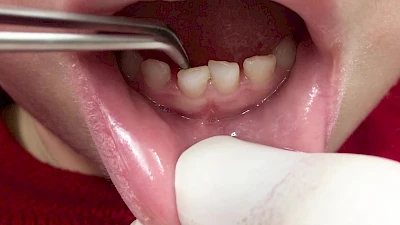

Eine geringe spürbare Beweglichkeit der Zähne ist durchaus normal, da Zähne über Fasern im Kieferknochen aufgehängt sind. Lassen sich Zähne, Kronen oder Brücken jedoch deutlich sichtbar bewegen, besteht die Gefahr, dass sie sich lösen und verschluckt oder aspiriert werden. Deshalb sollte in diesen Fällen der Zahnarzt verständigt werden.